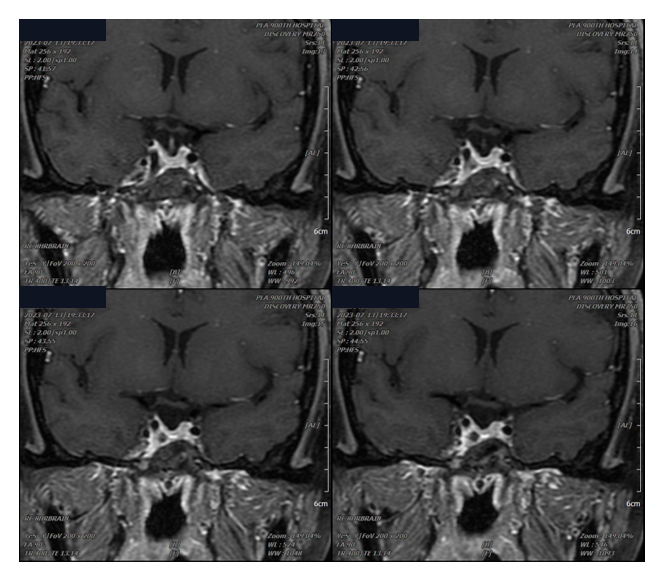

辅助检查:内分泌功能检测示GH >40 ng/ml,IGF-1 618 ng/ml,OGTT-GH >40 ng/ml。

患者经左侧鼻孔入路手术,切开海绵窦前下壁,依次切除垂体窝及右侧海绵窦内肿瘤,达次全切除(因ICA遮挡)。术后GH降至20 ng/ml。病理提示生长激素细胞腺瘤。因海绵窦前下壁为单层结构,极为薄弱,磨除骨质时易破裂。由于肿瘤侵犯海绵窦,术中继发性大出血虽较少见,但仍需警惕。通过尽可能扩大前下壁显露范围,即便未完全达到内镜可视化程度,仍可在切除内侧壁并部分开放前下壁的基础上,获得较充分的操作空间,从而较满意地切除外侧间隙内肿瘤。

术后病理示致密型生长激素细胞腺瘤,Ki-67约4%。术后1个月患者一般状况良好,OGTT-GH 6.2 ng/ml,IGF-1 675 ng/ml,开始接受SSA(奥曲肽)治疗。3个月复查提示生化缓解。缓解后出院随访,半年后复查出现异常,予以再次给药。1个月后(术后11个月,2022-08-16)OGTT-GH降至0.42 ng/ml,恢复正常;同期IGF-1为159 ng/ml(参考值116~358)。

术后3个月MRI增强显示治疗效果理想。2022-07-12(术后1年)MRI增强提示右侧海绵窦斑块状强化影,考虑复发。经规律SSA治疗后,肿块明显缩小。2025年1月随访:IGF-1 208 ng/ml,随机GH 0.216 ng/ml,病情稳定。